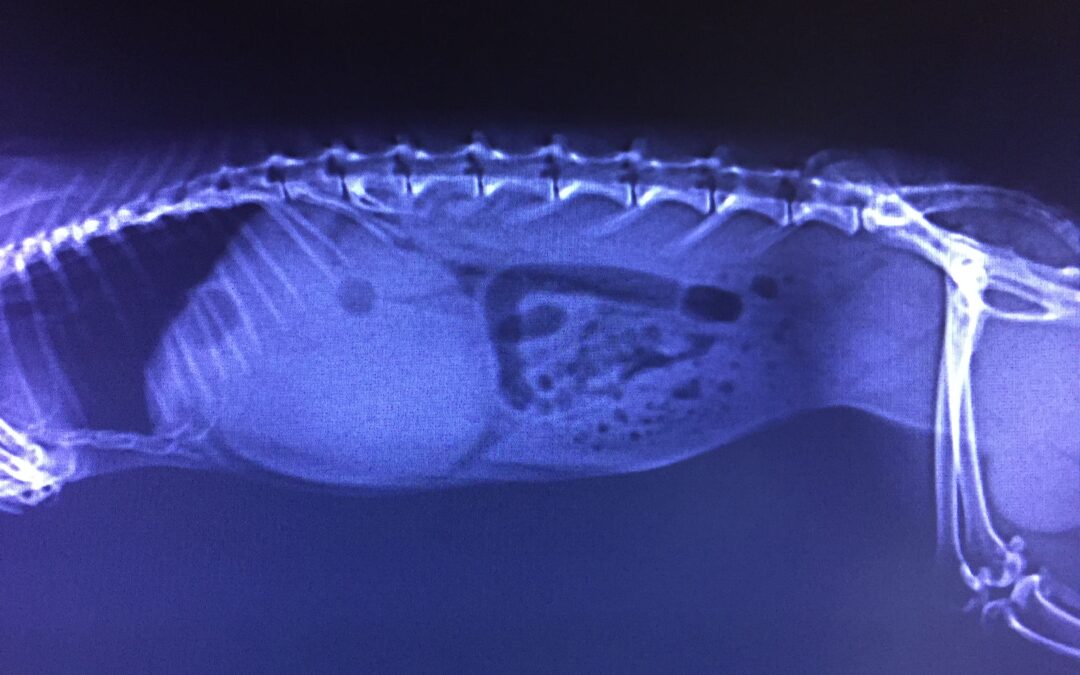

Ollie Drennan gut stasis